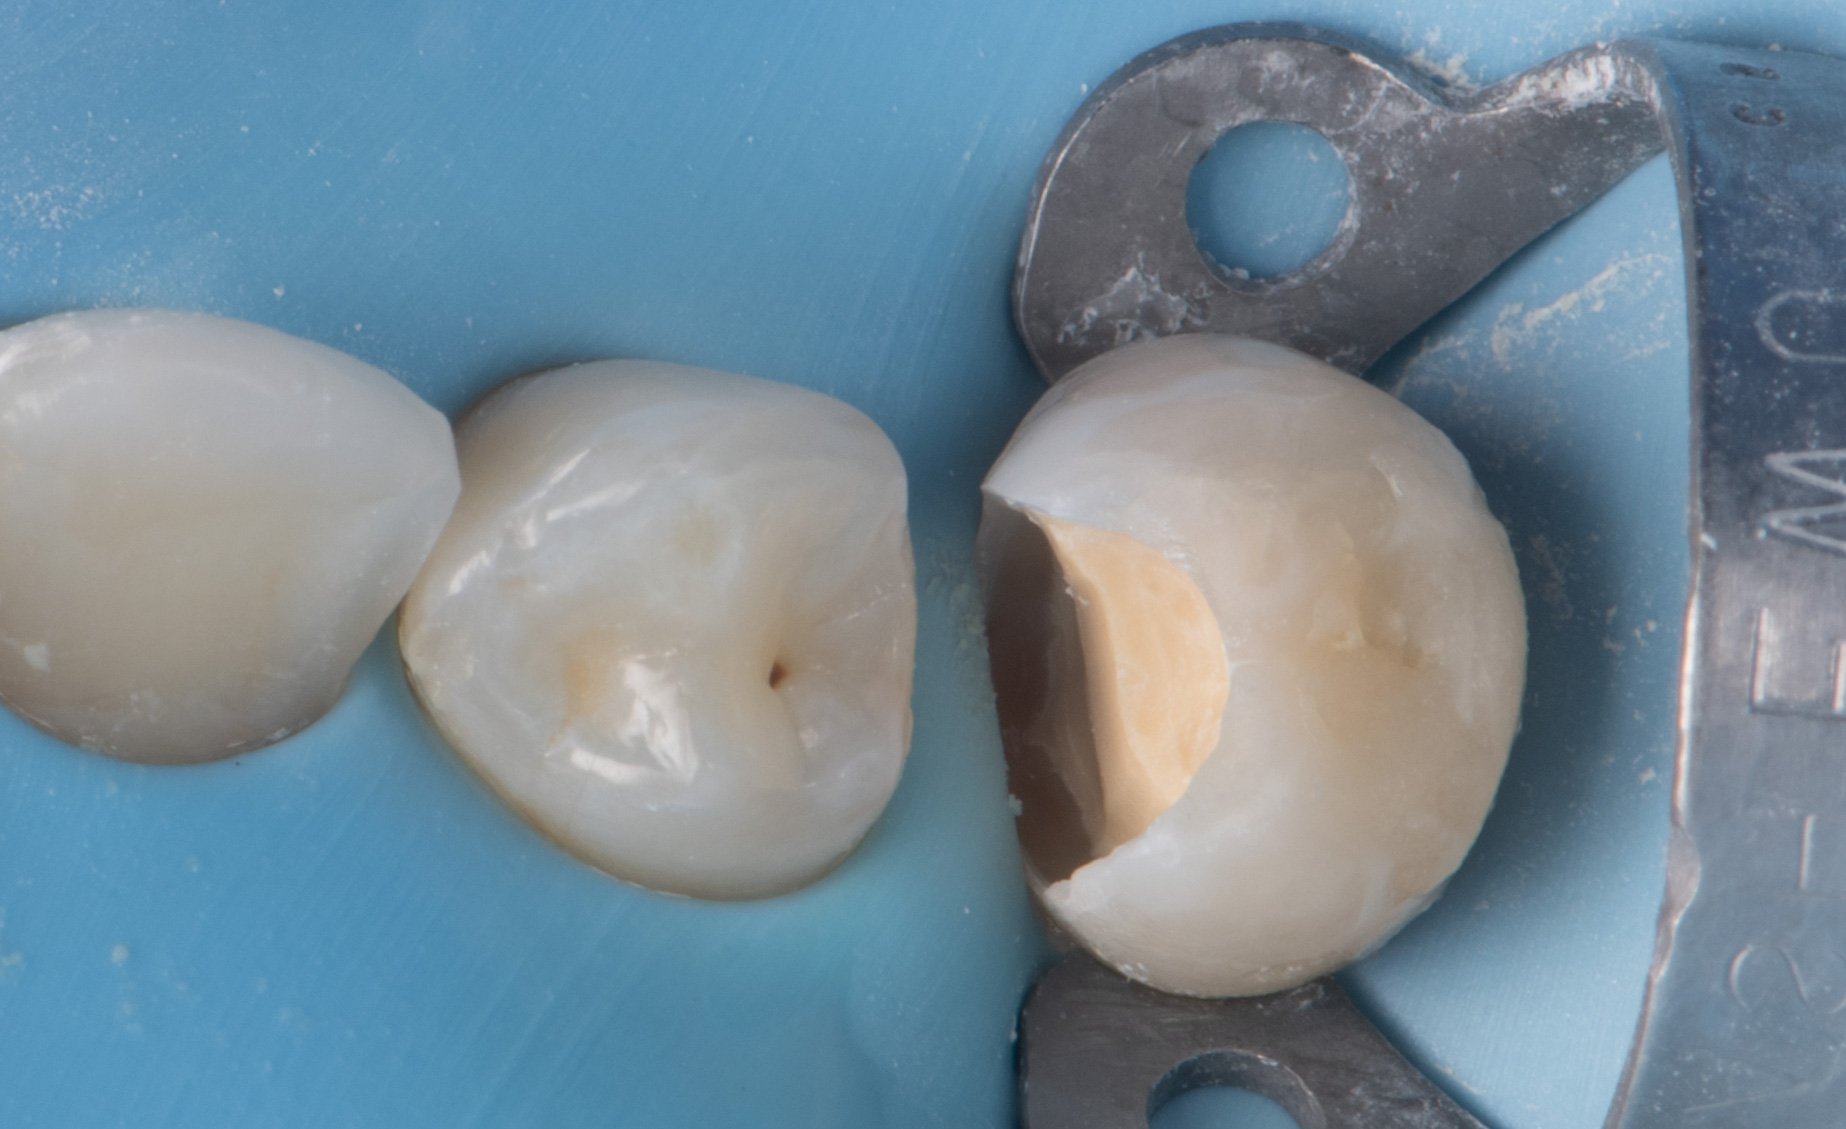

Hands-on training in het behandelen en restaureren van pulpa-exposities in molaren

De cursus bestaat uit een combinatie van interactieve theorie en praktische oefeningen. Er wordt gewerkt met preparatiemodellen waarin een diepe caviteit en pulpablootstelling wordt gesimuleerd.

Praktisch deel (hands-on):

• Preparatie van diepe caviteiten in molaren;

• Toepassing van pulpa-afdekmaterialen;

• Directe (diepe) adhesieve restauratie (composietopbouw);